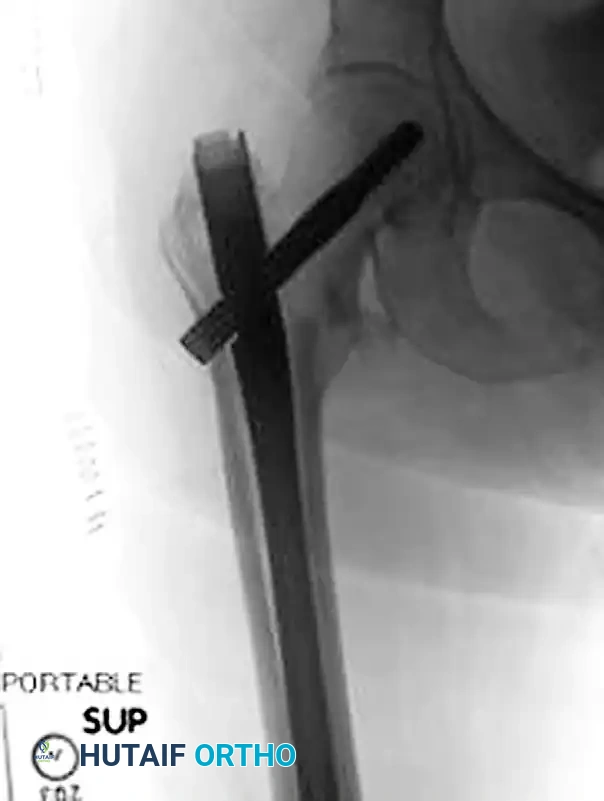

1. Guide Pin Insertion

- Place a 135-degree angled guide against the lateral femoral cortex.

- Insert a 2.8-mm threaded guide pin through the guide, aiming for the exact center of the femoral head on both the AP and lateral fluoroscopic views (the "center-center" position).

- To assist with anteversion alignment, a secondary guide pin can be placed anteriorly along the femoral neck.

- Advance the primary guide pin until its tip is approximately 5 mm from the subchondral bone of the articular surface.

2. Measurement and Reaming

- Measure the depth of the inserted guide pin using the specialized measuring gauge.

- Set the triple reamer to exactly 5 mm less than the measured depth.

- Ream over the guide pin. Crucial Step: Monitor the reaming process continuously under fluoroscopy to ensure the guide pin is not inadvertently advanced through the femoral head into the acetabulum or pelvis.

3. Lag Screw Insertion

- Select a lag screw that matches the measurement obtained from the triple reamer. If significant fracture impaction (shortening) is anticipated, select a lag screw that is 5 mm shorter to prevent the screw threads from bottoming out in the plate barrel.

- Using the insertion wrench, advance the lag screw into the femoral head. Remember that 90 degrees of rotation results in approximately 0.75 mm of advancement.

- Alignment: When the final depth is reached, the handle of the insertion wrench must be perfectly parallel to the axis of the femoral shaft (perpendicular to the floor in a lateral position). This aligns the flats of the lag screw shaft with the barrel of the side plate, allowing the plate to slide over the screw.

4. Plate Application

- Slide the side plate over the lag screw shaft and advance it onto the lateral aspect of the femur.

- Use a tamp to fully seat the plate barrel over the screw and flush against the lateral cortex.

- Remove the lag screw retaining rod, the insertion wrench, and finally, the guide pin.

5. Cortical Fixation and Compression

- Secure the side plate to the femoral shaft using a bone clamp.

- Drill, measure, tap (if necessary), and place two to four bicortical 4.5-mm cortical screws through the plate into the femoral shaft. If a screw was initially used to pull the plate to the bone, it may need to be exchanged for a shorter one once the plate is fully seated.

- Release the traction on the fracture table.

- If additional impaction is desired, insert a compression screw into the back of the lag screw. Alternatively, manual compression can be applied by gently pushing the leg proximally.